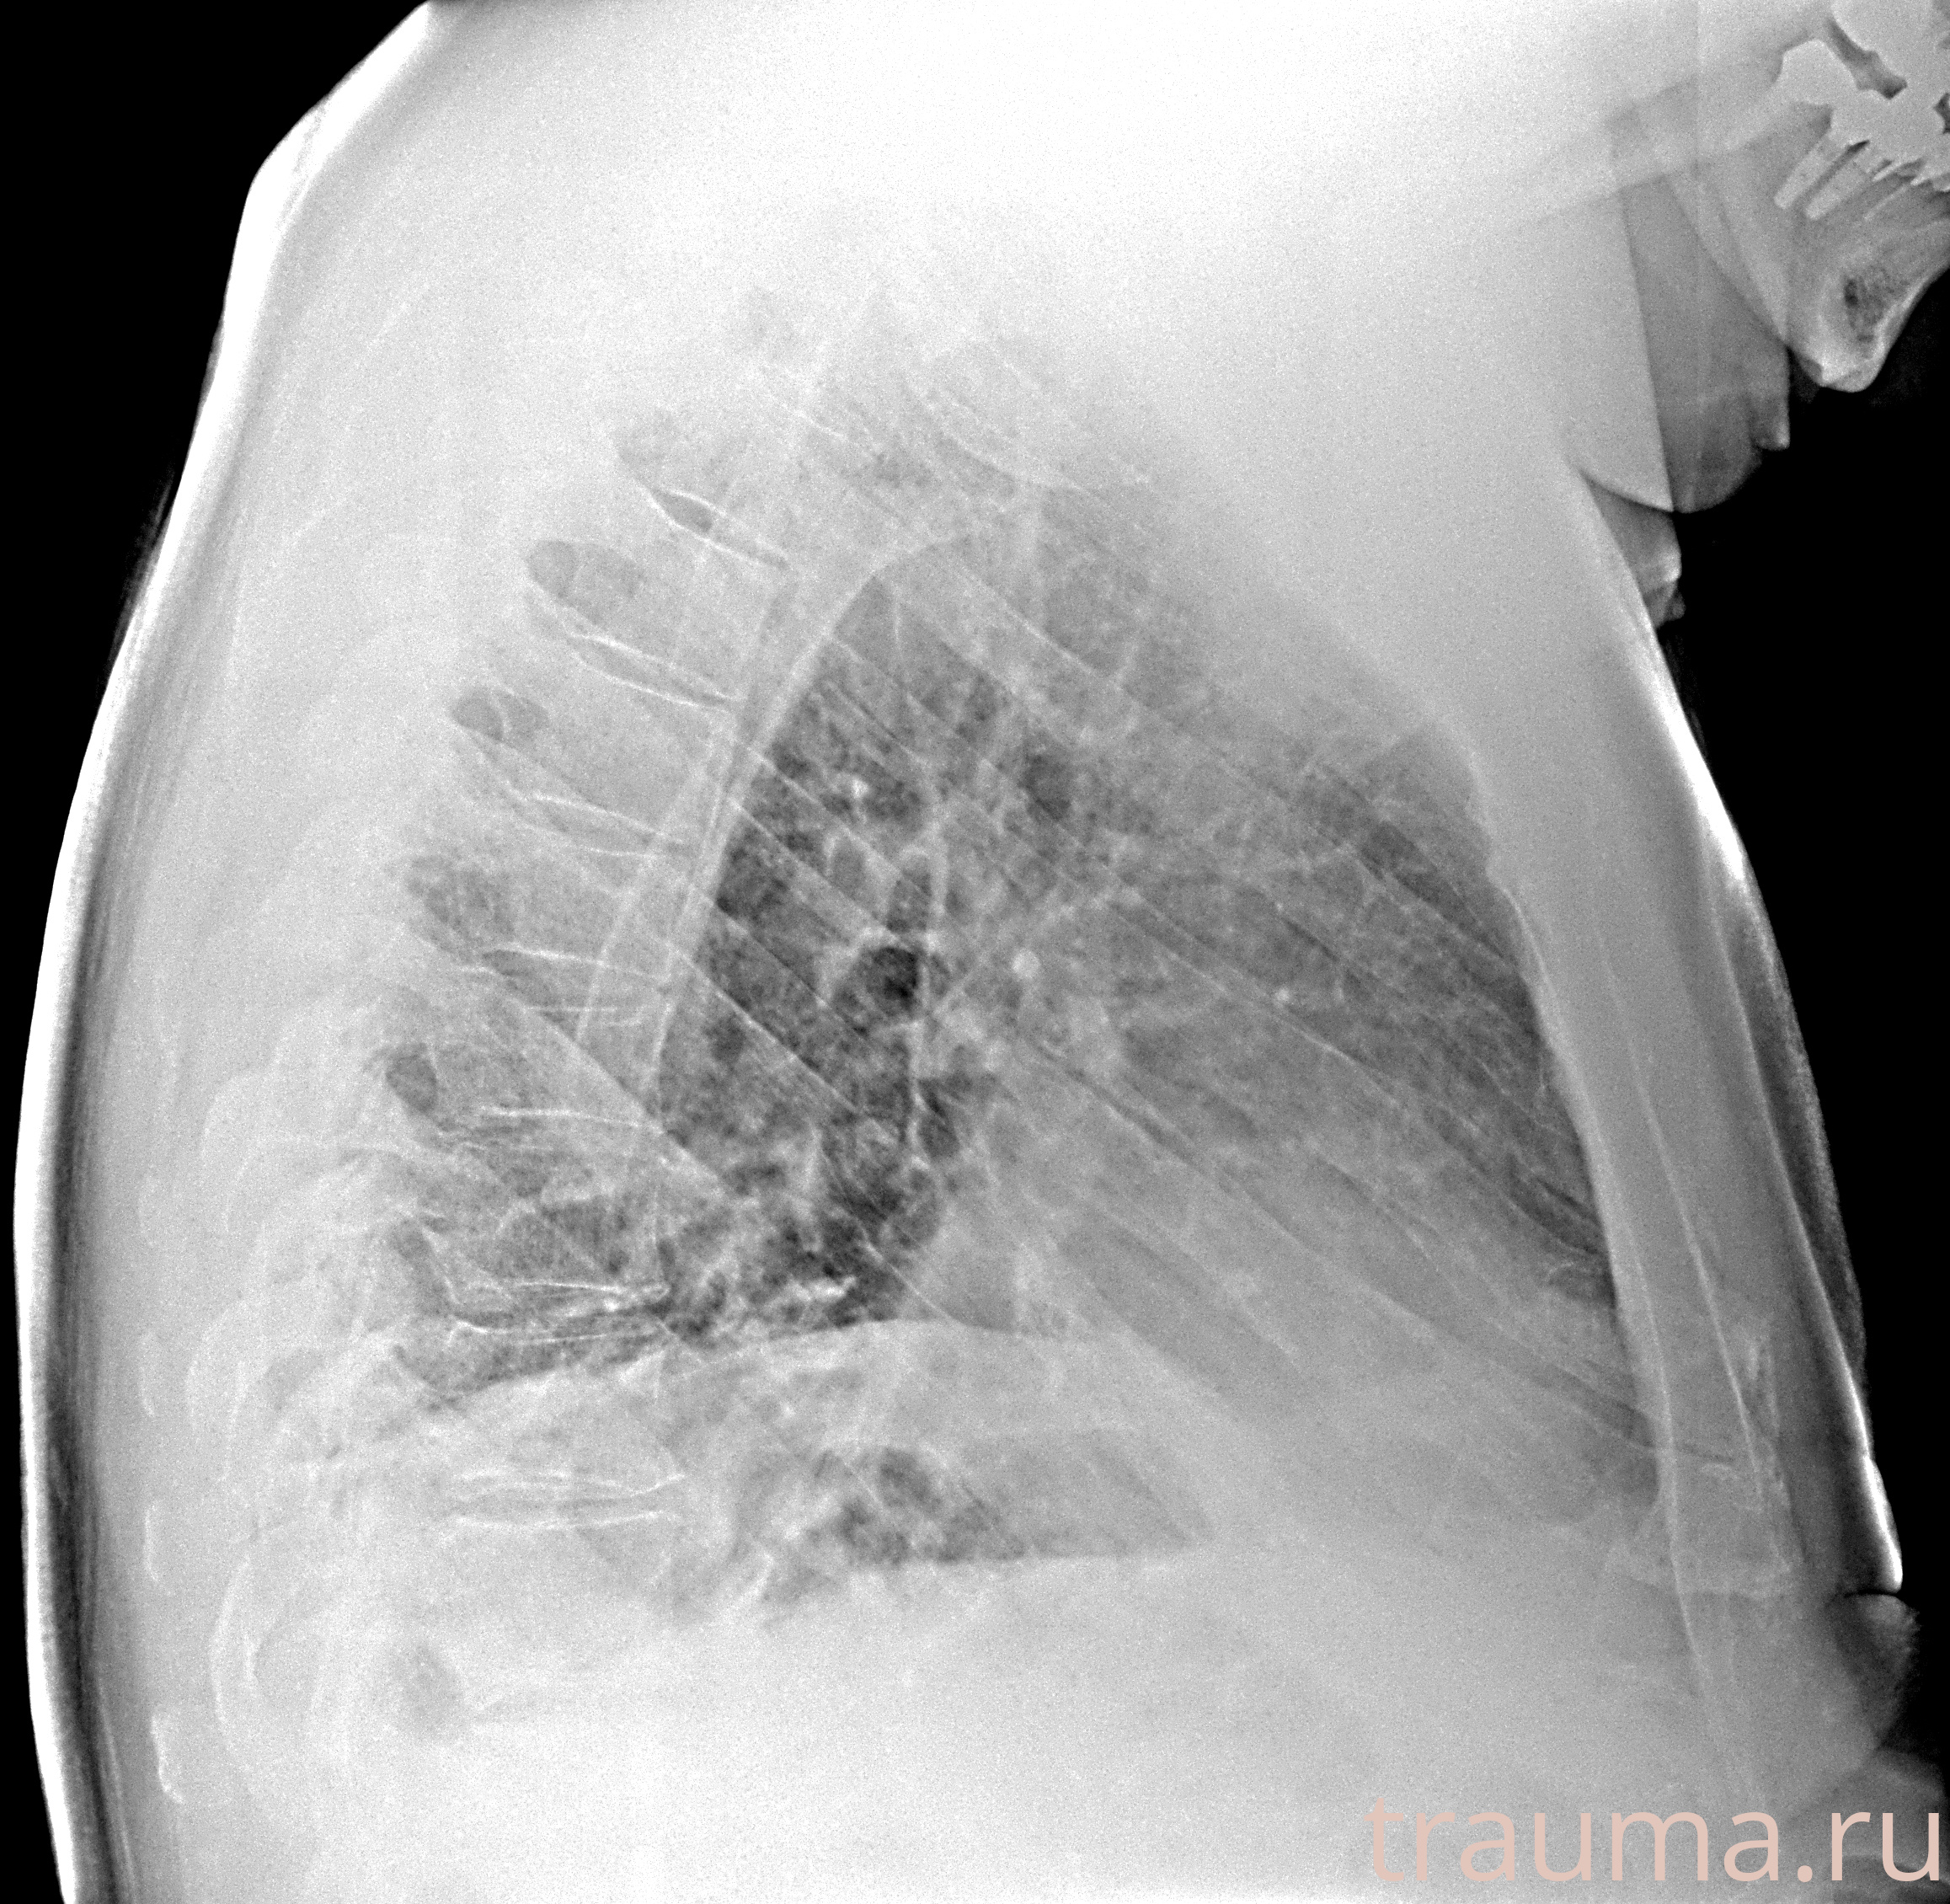

Рентгенограммы

Рентген на дому: по вашему адресу приезжает врач-рентгенолог, травматолог-ортопед с мобильным рентгеновским аппаратом, проводит диагностику травмы или заболевания, делает необходимые рентгенограммы, дает рекомендации по дальнейшему лечению. Получить качественные снимки в домашних условиях возможно благодаря уникальной методике, разработанной МосРентген Центром для института  Склифосовского